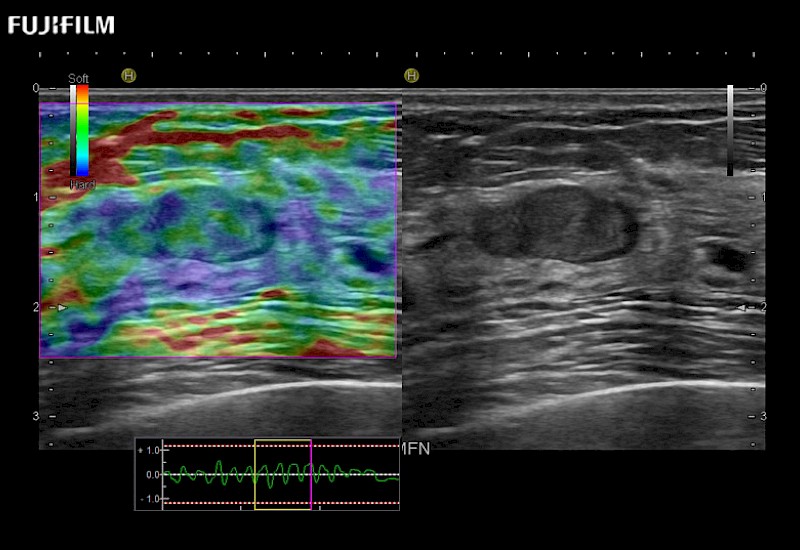

Extraordinary high-resolution digital imaging

Multi-Parametric imaging modalities

- Instant feedback on tumor margin delineation

- Valuable information to guide tumor resections

- Instant feedback on tumor margin delineation

- Instant feedback on tumor margin delineation